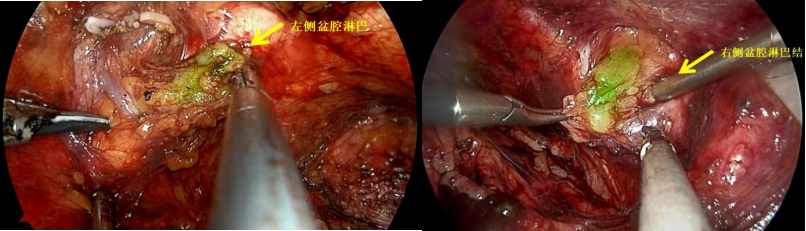

我院浦金贤教授团队,应用DGPR-1008(一种靶向PSMA的荧光造影剂,目前为临床试验阶段),术前静脉注射,荧光造影剂靶向定位至肿瘤病灶及转移淋巴结位置,多余造影剂经尿液代谢排出体外;术中开启近红外荧光模式后,前列腺癌灶、转移的淋巴结以及肿瘤侵犯转移的其他组织都会因结合了荧光造影剂而产生荧光,使得主刀医生能显著将其与周围正常组织区分开来,进而达到肿瘤彻底、精确、完全的切除。